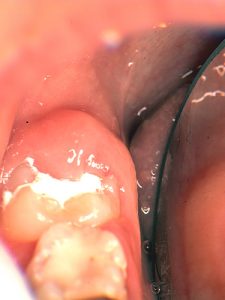

このようなメカニズムでタンニンは、“抗菌作用”・“抗酸化作用”を持っていたのです。ところでタンニンの抗菌性とフッ化物の歯質強化作用を期待して作られたのがHY剤含有のセメントです。さて筆者は、HY剤配合セメントをう蝕感受性の高い萌出途上歯のテンポラリー・シーラントとして利用してきました。(図1)このセメントについて最近、面白いことに気がつきました。それは、セメントの上には歯垢が付きにくいのです(図2)。そこで実験を行ってみました。

図1